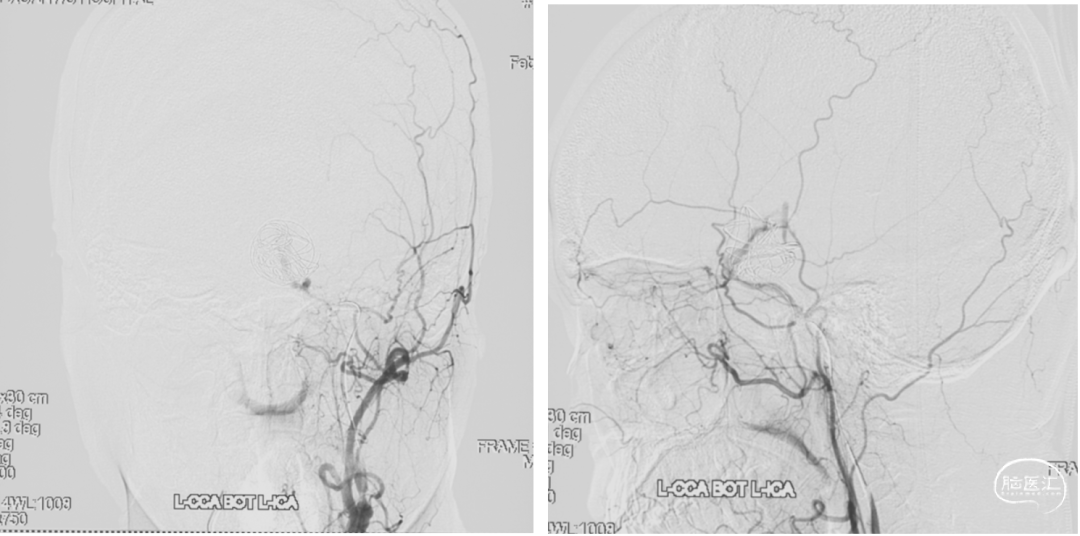

颈内动脉狭窄状况及闭塞试验

患者颞浅动脉、桡动脉较细,需行高流量+低流量搭桥维持大脑中动脉血流。

3. 术中:颞浅动脉-大脑中动脉搭桥,ICG显示血流通畅。

4. STA-M4(额叶分支),补充血流,增加高流量搭桥时M2段阻断的耐受性。

5. 术中:颈外动脉(ECA)-桡动脉(RA)-大脑中动脉(MCA)M2段搭桥,ICG显示血流通畅。

1. 术后一周复查DSA显示动脉瘤无血流,桥血管通畅。